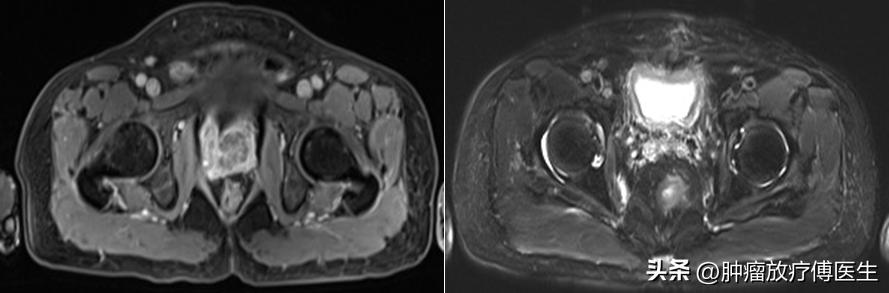

二、调强放疗联合内分泌治疗:2014年4月4日在我科行前列腺癌根治性调强适形放射治疗(图2、3),考虑患者出现淋巴结转移,故给予大范围照射,靶区包括前列腺及双侧精囊,肿瘤照射剂量72Gy/2Gy/36F,盆腔转移淋巴结,肿瘤照射剂量60Gy/2Gy/30f,盆腔淋巴结引流区,肿瘤照射剂量54Gy/1.8Gy/30W。放射治疗同时给予“比卡鲁胺50mg口服1次/日”内分泌治疗。放射治疗结束复查PSA 0.02ng/ml,睾酮<10ng/dl,提示放射治疗有效。

图2 放射治疗前后盆腔MRI对比(左:放疗前2014-2 ;右:放疗后2014-06)